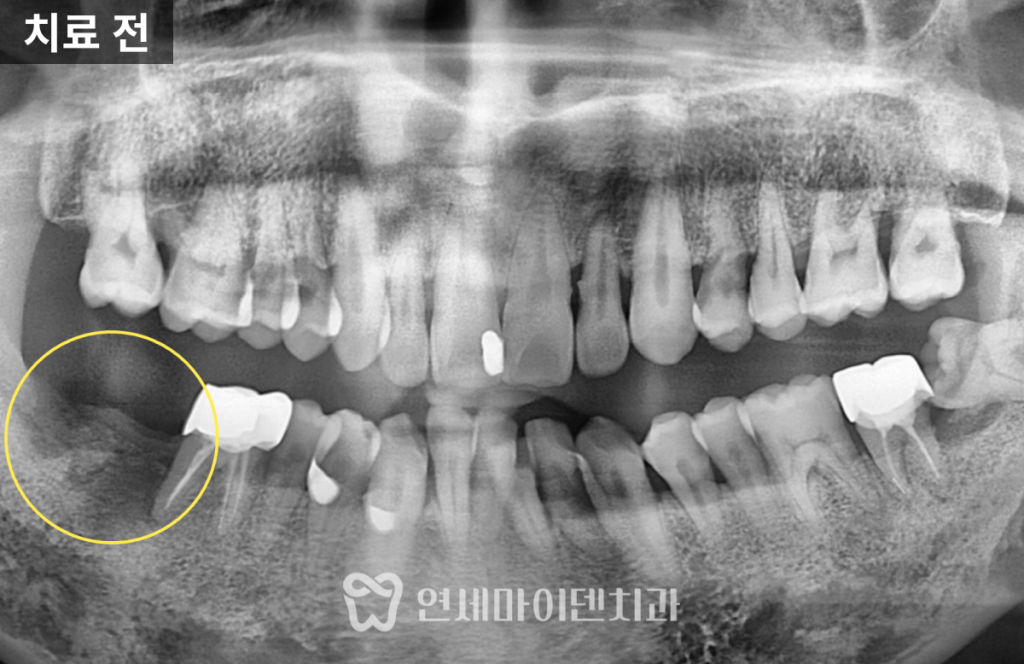

앞 치아는 자연치로 살렸습니다.발치 후 상태와 문제점

환자분은 오랫동안 통증을 참고 지내다

결국 어금니 하나를 발치한 상태로 내원하셨습니다.

X-ray를 확인해보면,

반대편 어금니는 뼈 상태가 비교적 건강한 반면문제 부위는 치조골 높이가

절반 가까이 무너진 상태였습니다이 때문에 이전 병원에서는

“앞 치아도 곧 못 쓴다”며

두 개 모두 임플란트를 권유받았던 상황이었습니다.

하지만, 앞쪽 어금니의 경우

뿌리 앞쪽 뼈는 비교적 단단하게 남아 있었고

염증 범위도 제한적이어서

충분히 보존 가능성이 있는 상태였습니다.즉,

무조건 두 개를 다 뽑아야 할 상황은 아니었습니다.치료 방향: “하나는 살리고, 하나는 심자”

그 결과,

수술 후 X-ray에서 뼈 높이가 뚜렷하게 상승했고

앞쪽 어금니의 흔들림도 눈에 띄게 줄어들었습니다.3년 경과 후 결과

치료 후 3년이 지난 현재까지도

임플란트, 보존한 자연치

모두 안정적으로 유지되고 있습니다.초기에는 뼈가 절반밖에 남지 않았던 부위가

뼈이식 후 건강한 높이로 회복되었고,

그 결과 임플란트 하나가

옆 자연치의 수명까지 함께 늘려준 셈이 되었습니다.